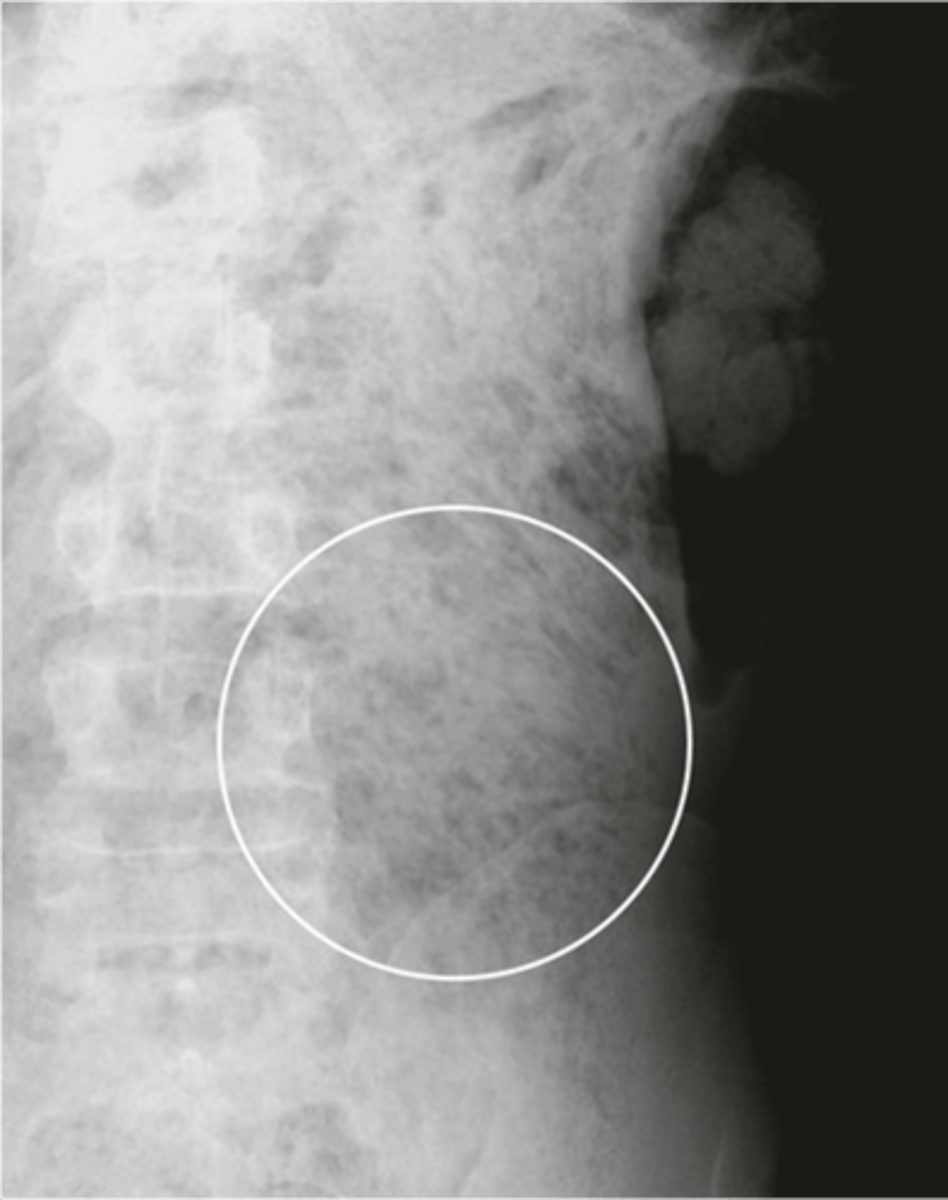

What view is this image in?

upright view of the abdomen

good for seeing free air in the peritoneal cavity

good for seeing air-fluid levels within the bowel

what is abnormal about the circled area?

free air in the peritoneum under the diaphragm